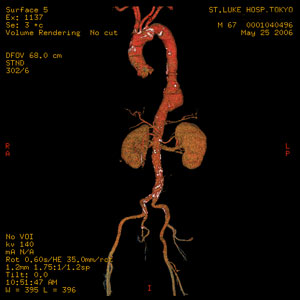

症例6

67歳 男性

検診異常

【起始・経過】

平成15年より腹部大動脈瘤を指摘。

平成18年1月CTにてφ5cm大のAAAを認め7月当院紹介受診。

【既往歴】

56歳 AMI→PCI

64歳 Rectal Ca→ope

高血圧(+) 糖尿病(−) 喫煙歴(15本×30年)

【治療計画】

Cook Zenith AAA stent graft